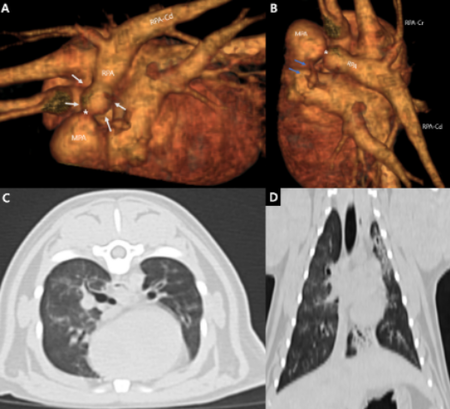

■ 편측성 폐동맥 협착증·폐동맥 형성부전증 고양이 ‘풍선 성형술’로 교정

세 번째 논문은 편측성 폐동맥 협착증과 반대편 폐동맥 형성부전증이라는 복합 심폐기형을 가진 4개월령 고양이에서 풍선 성형술로 치료한 후 장기 예후를 추적한 증례로 'Journal of Veterinary Medical Science(SCI)'에 게재됐다.

해당 환자는 4개월령 고양이로 심장 초음파에서 우측 폐동맥 가지의 폐색과 편측 폐동맥 무형성이 확인됐으며, 협착부 해소를 위한 풍선확장술을 실시했다. 시술 후 압력경사는 31.19 mmHg (velocity: 2.79 m/s)로 감소했으며, 1년 후 재검에서는 우심실의 비대 및 우심방 확장 소견도 개선되어 심장이 정상화 됐다.

해당 환자는 추적 관찰된 3년간 무증상으로 투약 없이 지내고 있다. 해당 연구는 드문 선천성 심폐기형에 대한 성공적인 인터벤션 치료와 장기 예후를 제시한 사례로, 향후 유사 질환 치료에 중요한 참고자료가 될 것으로 기대된다.